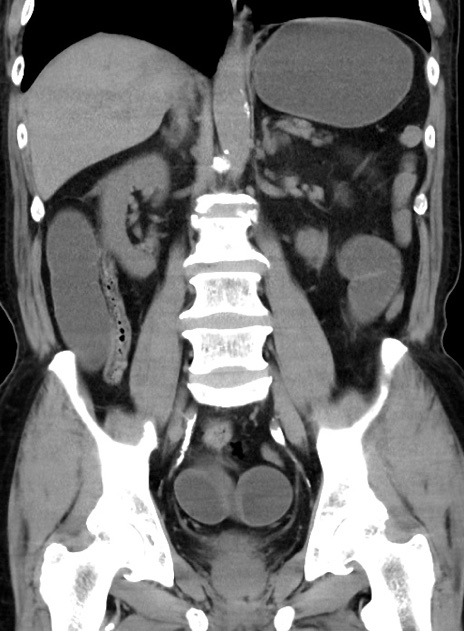

症例38(冠状断像)

【症例】70歳代 男性

【主訴】腹痛・嘔吐

【現病歴】昨晩より、嘔吐・腹痛あり。今朝になっても嘔吐あり。来院。

【既往歴】心臓バイパス手術、開腹胆摘、腸閉塞

【身体所見】BP 107/71mmHg、HR 116/min、腹部:平坦、軟、下腹部に軽度圧痛あり。反跳痛なし。

【データ】WBC 15100、CRP 0.32